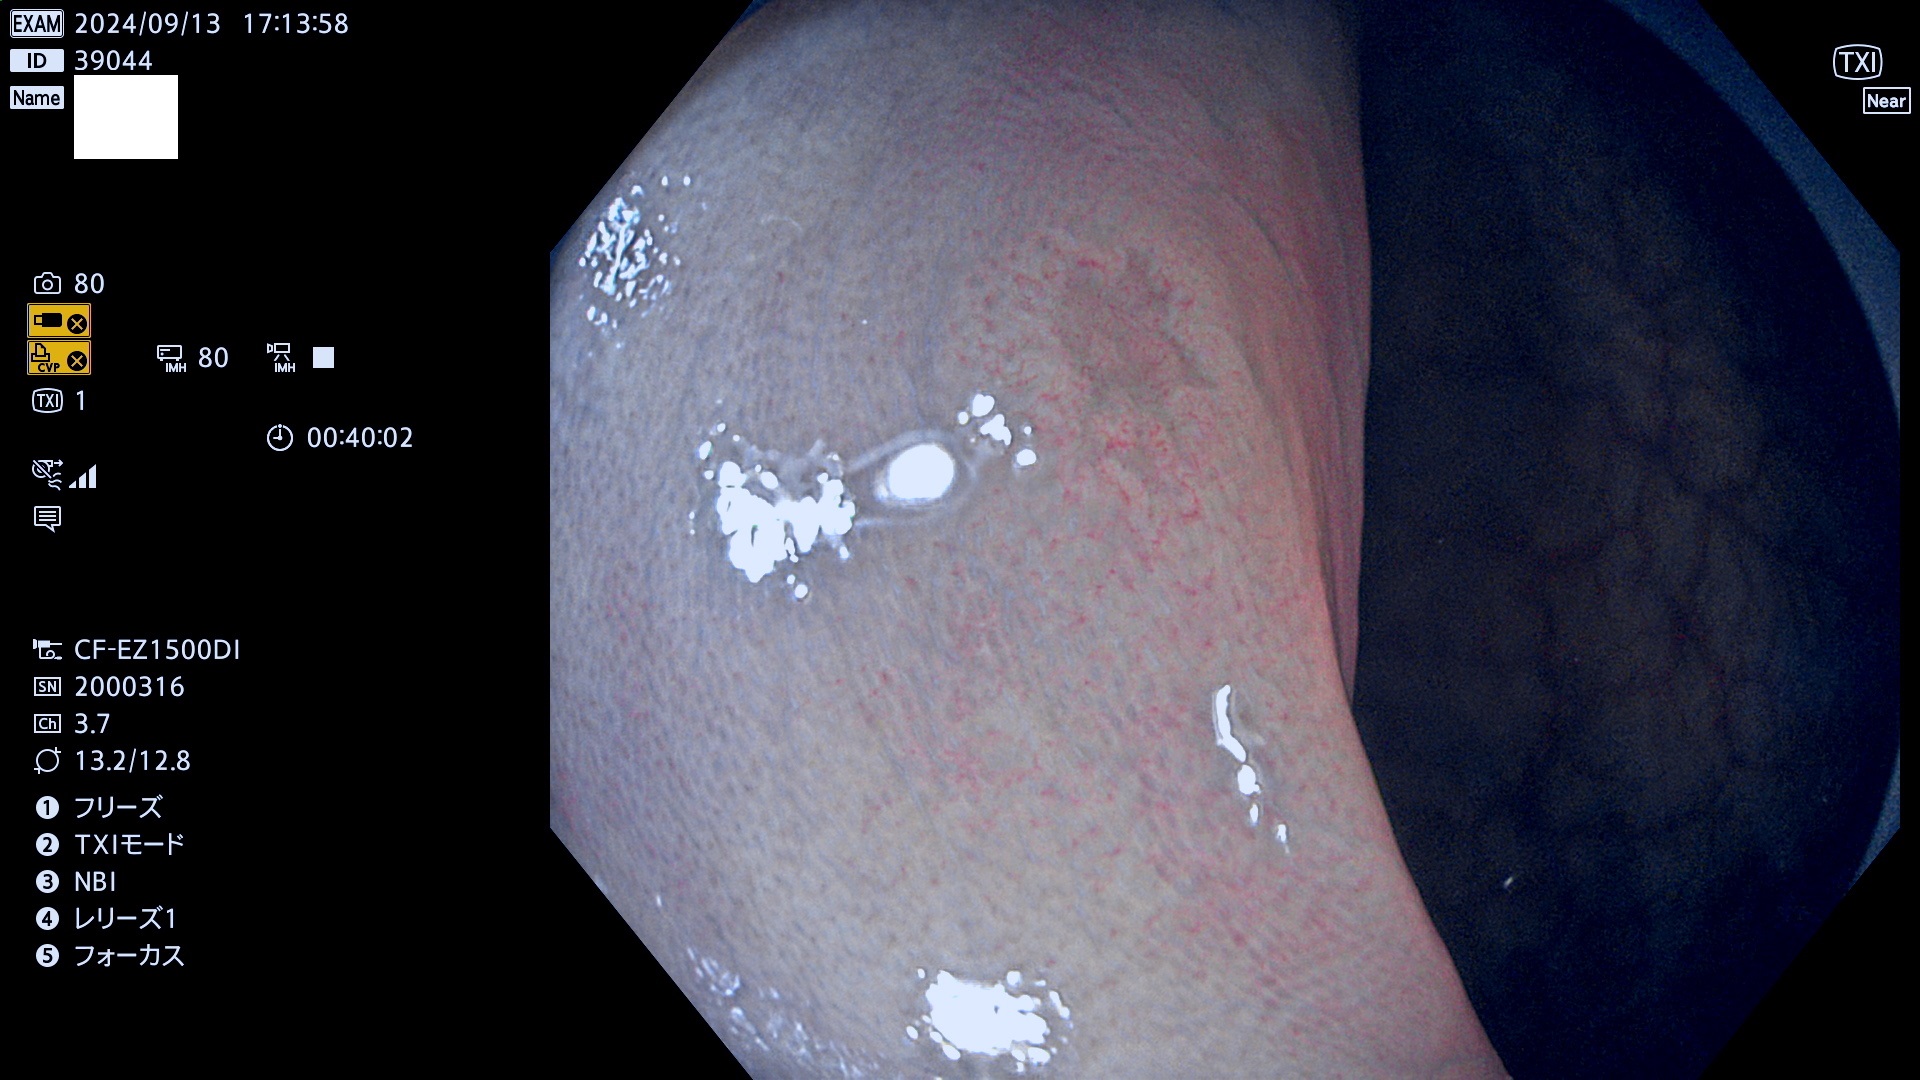

完全に平坦な物をUb、陥凹している物をUcと呼びます。最も発見が難しく危険な病変です。

毎週の検査(木・金・土・日)に発見されたUb、Uc型・腺腫を、その週の日曜の夜にUPし1週間、提示します。

抽出の対象期間 2024年9月12日〜9月15日の4日間(45件の検査)9件 (9/45=20%)